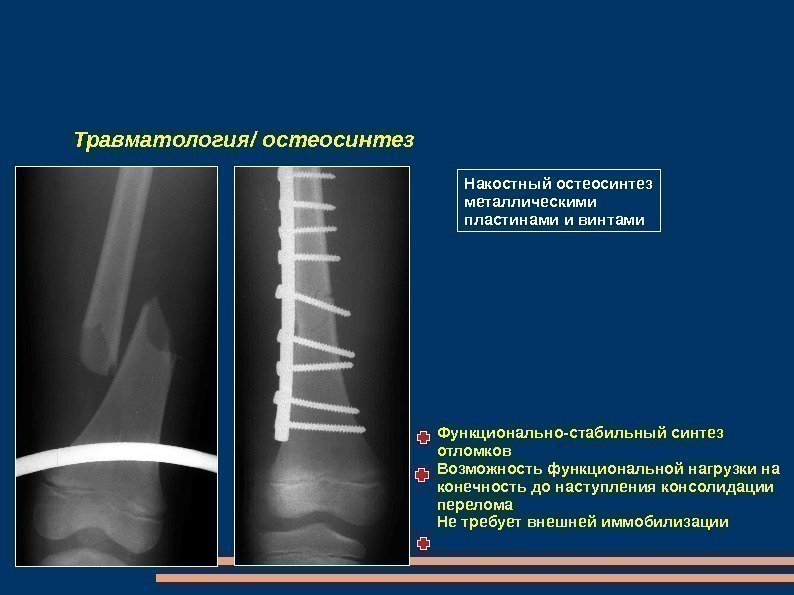

Травматология/ остеосинтез Накостный остеосинтез металлическими пластинами и винтами Функционально-стабильный синтез отломков Возможность функциональной нагрузки на конечность до наступления консолидации перелома Не требует внешней иммобилизации